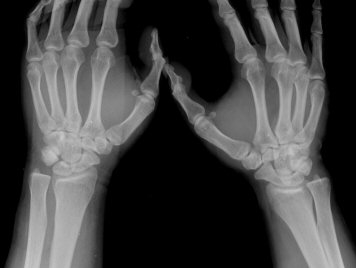

ÁÖ»ó°ñ ¼±»ó°ñÀýÀº ´Ü¼ø¹æ»ç¼± ÃÔ¿µ ½Ã È®ÀεÇÁö ¾ÊÀº °æ¿ì°¡ ¸¹Àºµ¥ ÀÌ ¶§ ÃÊÀ½ÆÄ

°Ë»ç°¡ ÁÖ»ó°ñ °ñÀý Áø´Ü¿¡ ¸Å¿ì À¯¿ëÇÏ´Ù. ±×·¯¹Ç·Î ¼Õ¸ñ ´ÙÄ£ ÈÄ Áö¼ÓÀûÀÎ ÅëÁõÀ»

È£¼ÒÇϰí ÁÖ»ó°ñ ºÎÀ§ ¾ÐÅëÀ» º¸ÀÌ´Â °æ¿ì ÃÊÀ½ÆÄ°Ë»ç¸¦ ½ÃÇàÇÏ¿© ÁÖ»ó°ñ °ñÀý ¿©ºÎ¸¦

È®ÀÎÇØ¾ß ÇÑ´Ù.

ÃÊÀ½ÆÄ°Ë»ç¸¦ ½ÃÇàÇÒ ¼ö ¾ø´Â °æ¿ì´Â ÄÄÇ»ÅÍ ÃÔ¿µ°Ë»ç¸¦ ÁÖ»ó°ñ °ñÀýÀ» È®ÁøÇÒ ¼ö ÀÖ´Ù.